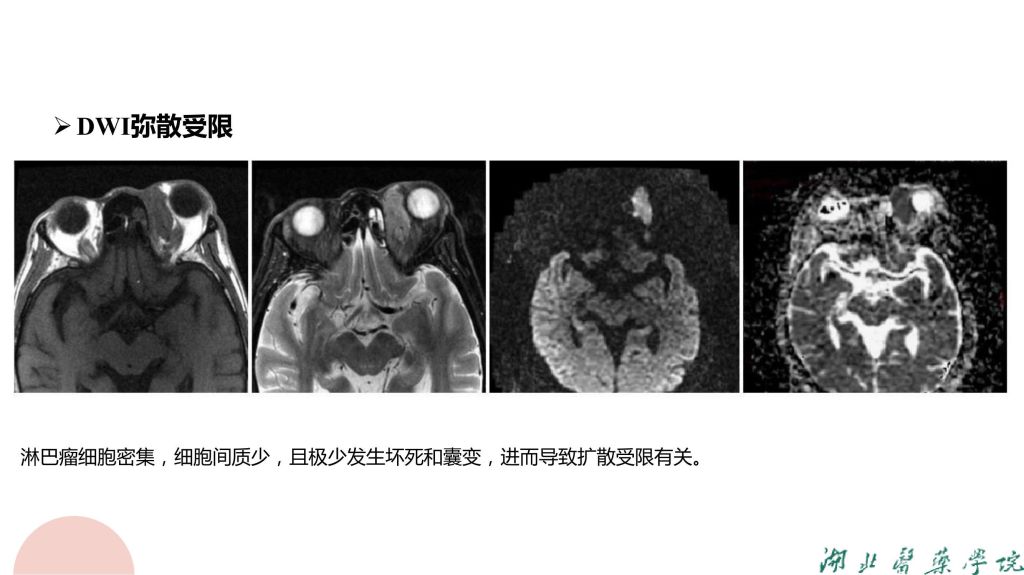

病例分析-眼眶淋巴瘤